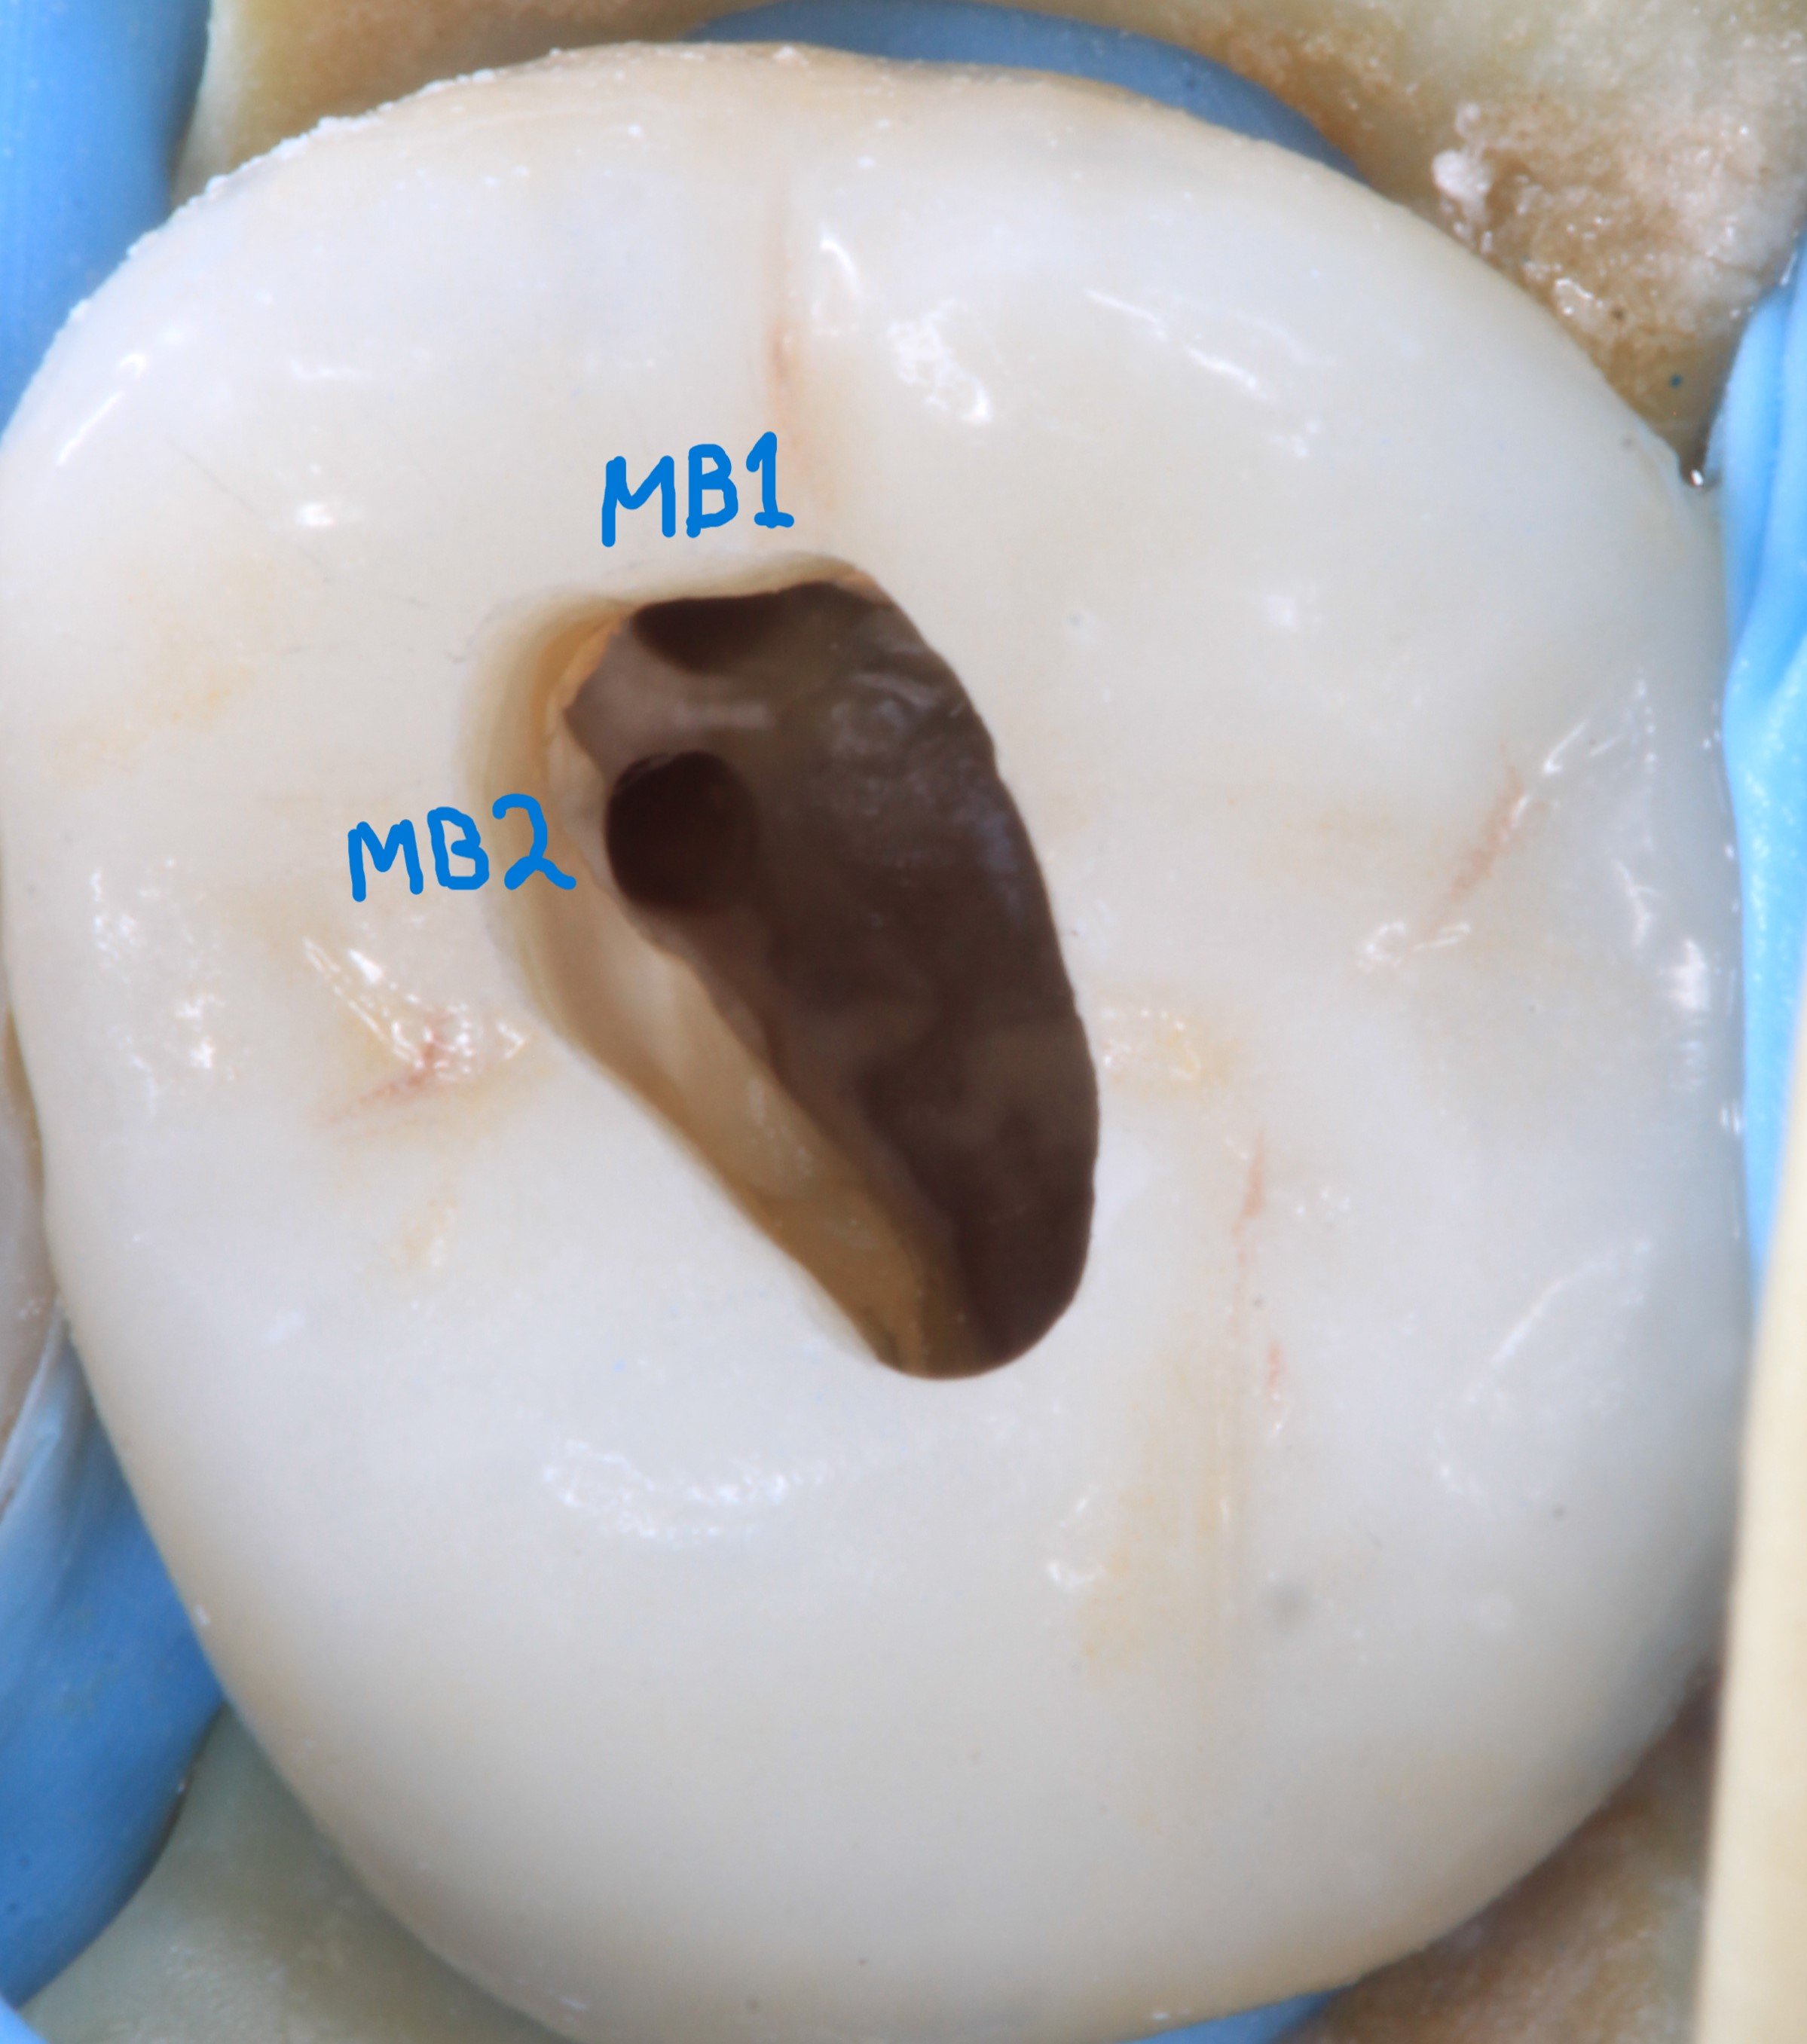

Access made through crown. Some exploration needed to find MB1 and MB2 canals.